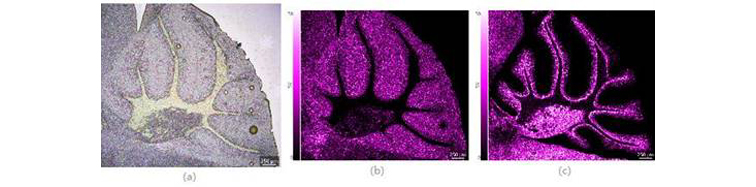

图3 小鼠脑切片(整体)光学图像及质谱图像 (a) 光学图像;(b) PI(38:4)的质谱图像;(c) Sulfatide (C24:1)的质谱图像,空间分辨率15μm

根据检测区域的大小及检测目标,可选择显微镜的不同放大倍数拍摄微小部位更加清晰的光学图像并进行高空间分辨率的成像质谱分析。通过质谱图像与光学图像的准确叠加,判断化合物的真实分布位置。对小鼠小脑区域进行空间分辨率为5μm的高空间分辨率检测,采集区域包括662x595, 共393,890像素点,检测时间约为2.2小时。

图4 小鼠脑切片(局部:小脑)光学图像及质谱图像 (a) 光学图像;(b) PI(38:4)的质谱图像;(c) Sulfatide (C24:1)的质谱图像,空间分辨率5μm